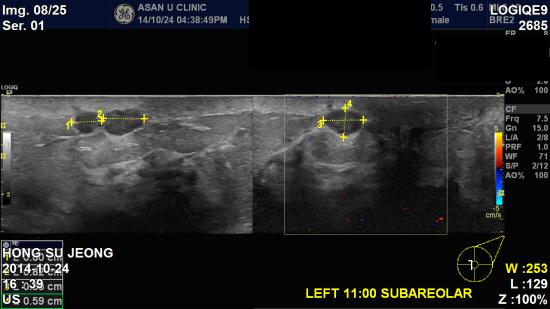

초음파상 좌측 11시방향 0.82cm, 10시 방향 3.34cm 미

좌측 겨드랑이 림프절 비대소견으로

조직검사 및 세침검사 시행 하여

침윤성 유관암 및 겨드랑이 전이로 진단 되었습니다.